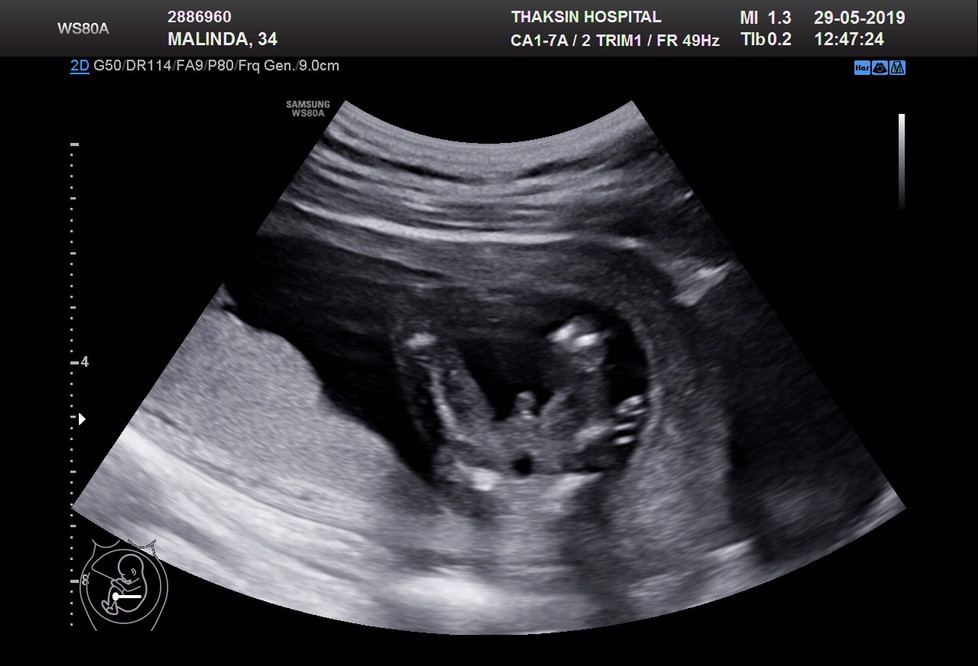

29+2W ชายค่ะ